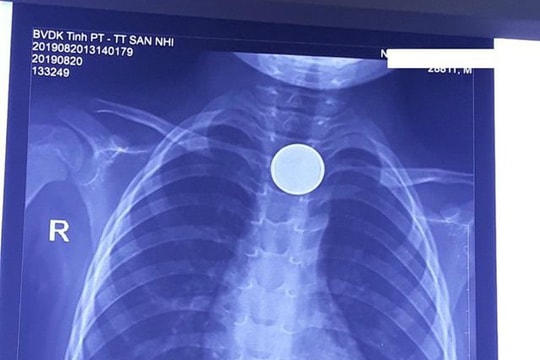

Gắp đồng xu ra khỏi thực quản bé trai 3 tuổi

Trên phim chụp Xquang cho thấy hình ảnh dị vật là 1 đồng xu mắc ở 1/3 phần trên của thực quản. Các bác sĩ đã phối hợp với các bác sĩ ngoại khoa để tiến hành nội soi can thiệp gắp dị vật ra khỏi cơ thể.